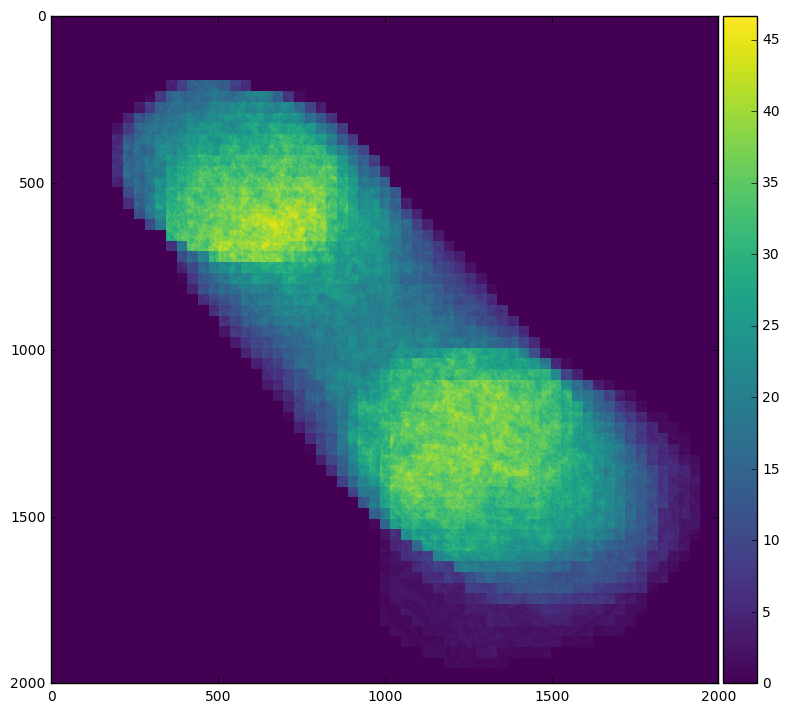

For example we can easily see our field of interest move across the frame by averaging across time:

skimage.io.imshow(stack.mean(axis=0).compute())

Or we can see when the field of interest is actually present within the frame by averaging across x and y

plt.plot(stack.mean(axis=[1, 2]).compute())

By looking at the profile plots for each case we can see that averaging over time involves much more inter-node communication, which can be quite expensive in this case.